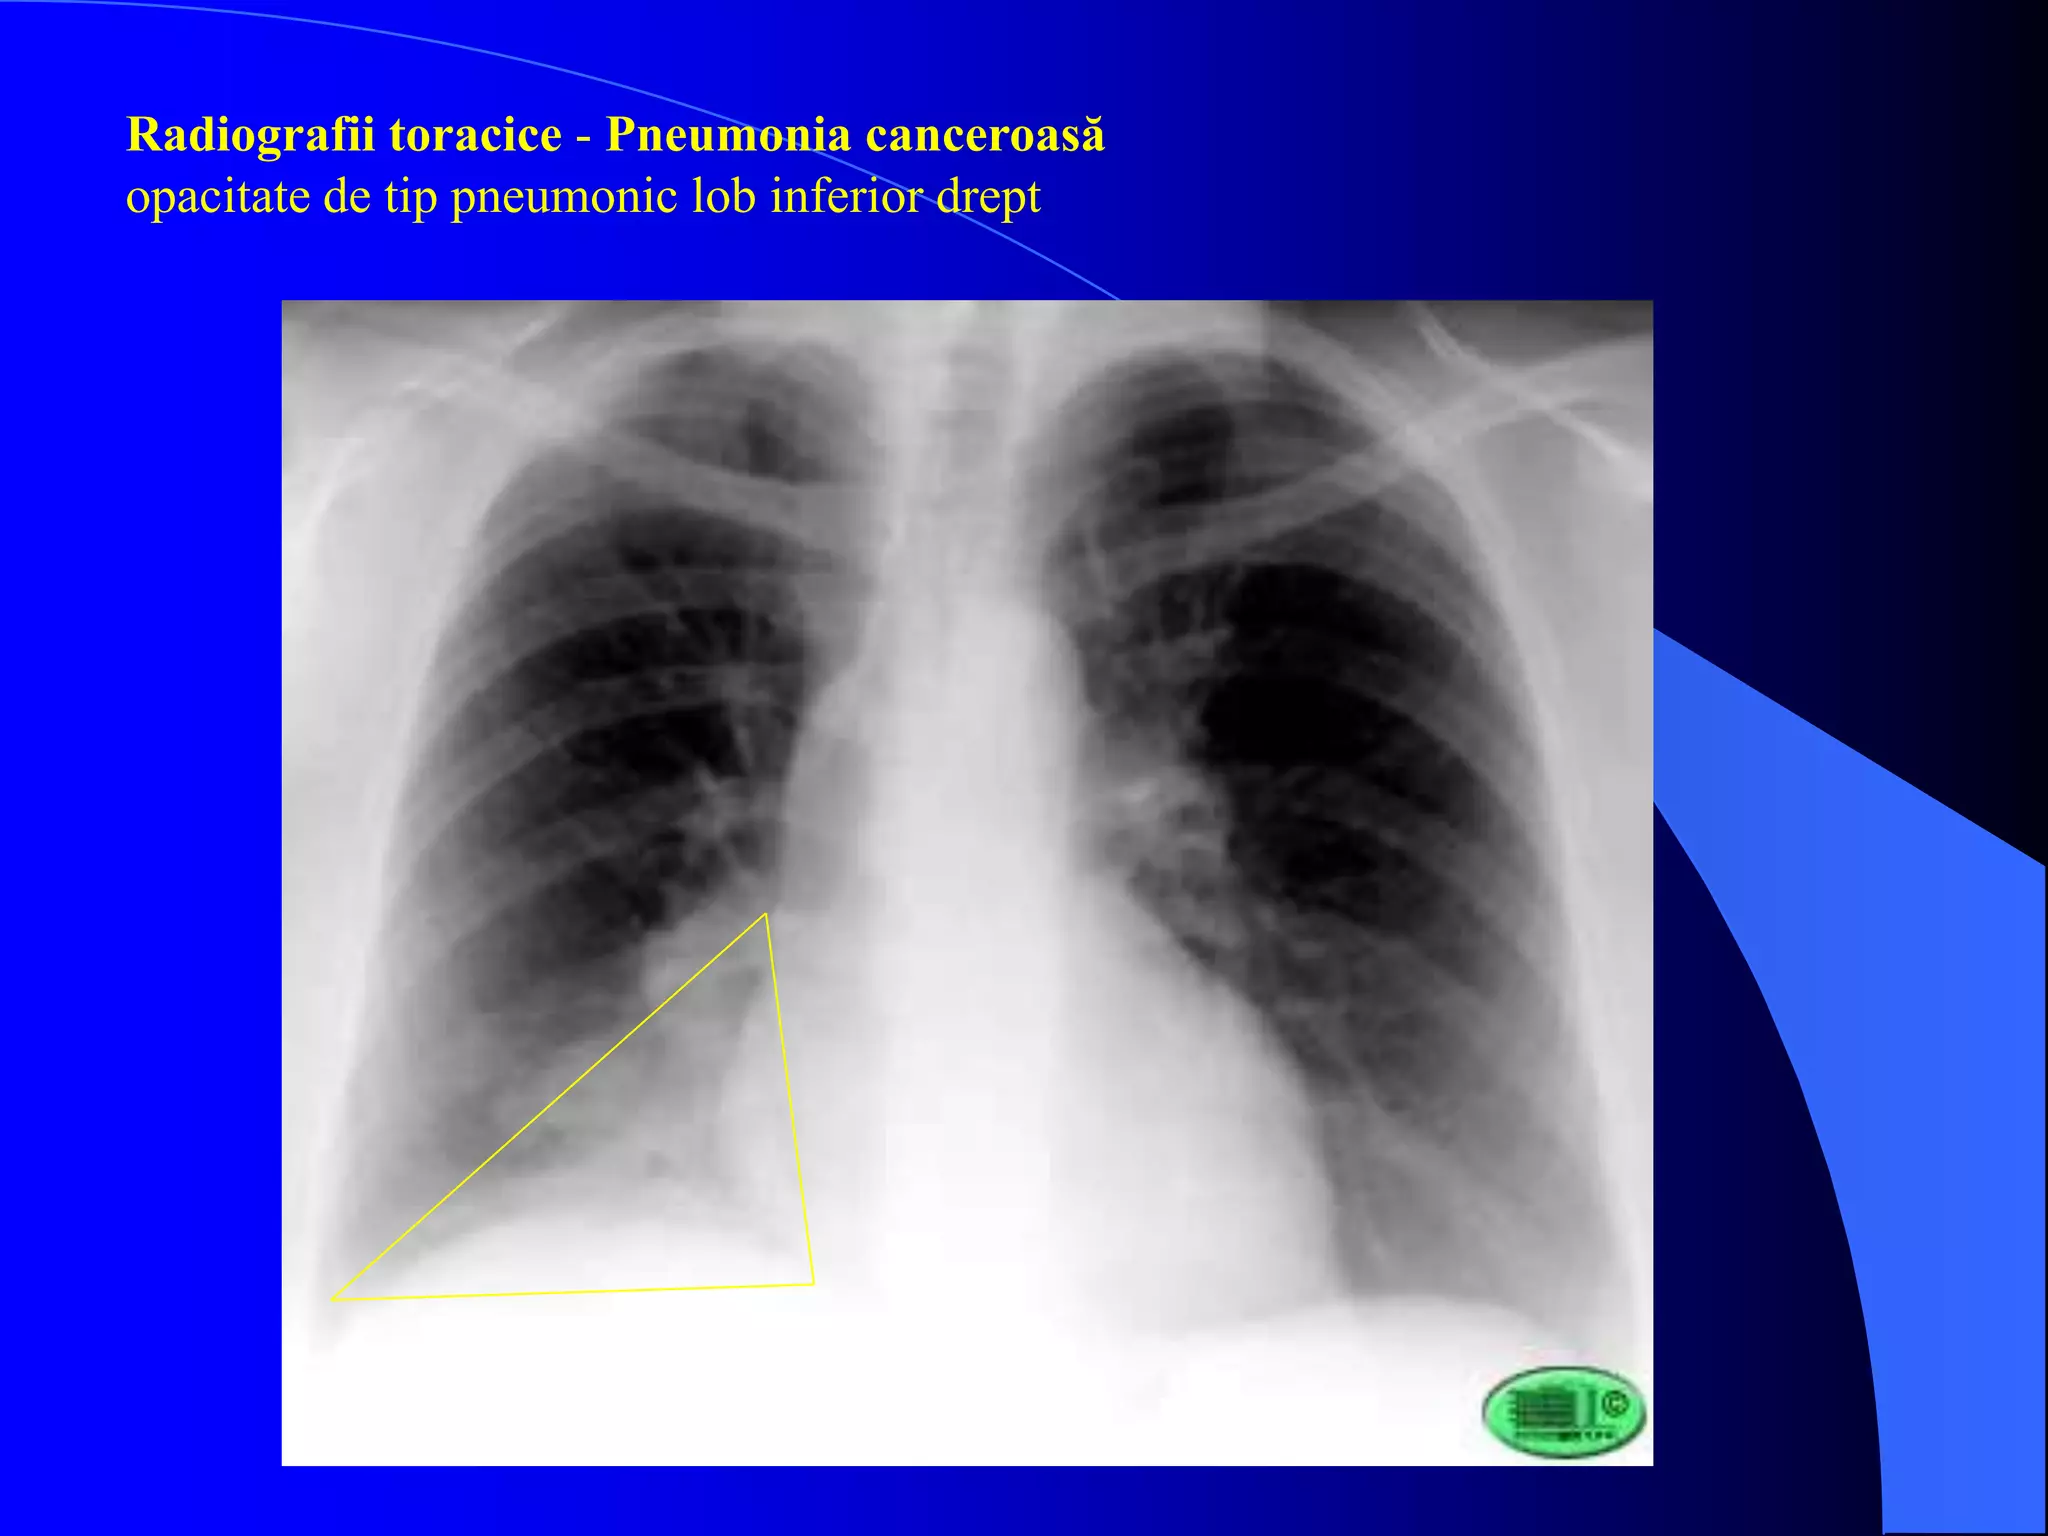

Radiografii toracice - Pneumonia canceroasă

opacitate de tip pneumonic lob inferior drept